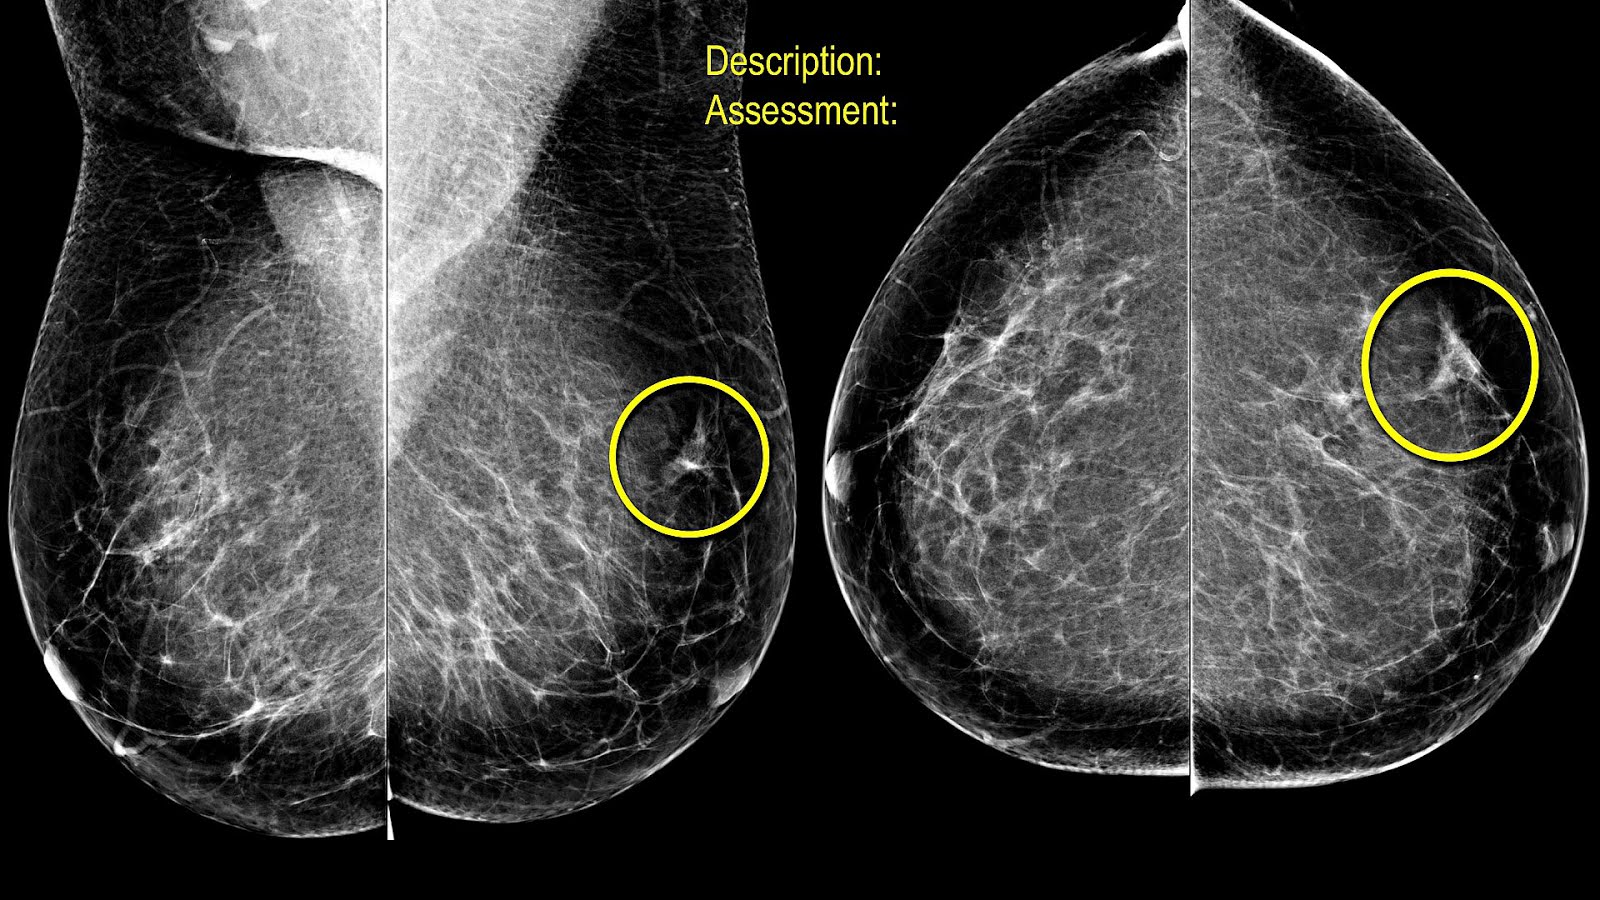

La mastografía está diseñada para identificar masas y cambios en el tejido mamario que podrían indicar la presencia de células cancerosas. Su capacidad para detectar estas anomalías en las etapas iniciales es esencial para un tratamiento efectivo y una recuperación exitosa.

La mastografía también es eficaz en la detección de microcalcificaciones, pequeños depósitos de calcio que pueden indicar la presencia de células anormales. La identificación temprana de estas microcalcificaciones es crucial para la evaluación y la toma de decisiones médicas.

Además, la mastografía evalúa la densidad mamaria, que puede variar entre las mujeres. La densidad mamaria puede afectar la visibilidad de posibles problemas, y la mastografía ayuda a los profesionales de la salud a adaptar su enfoque según esta característica única.

La mastografía digital ha superado a la mastografía convencional en muchos aspectos. Proporciona imágenes más nítidas y la capacidad de ajustar la exposición, mejorando así la capacidad de detectar incluso las anomalías más pequeñas.